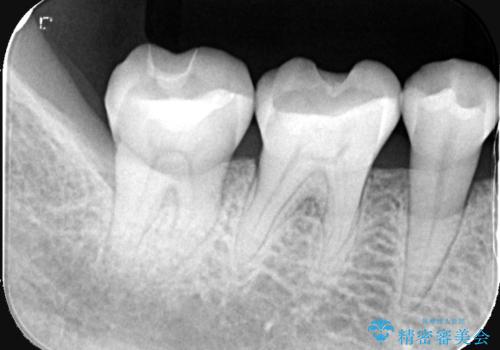

- 主訴:プラスチックの劣化が気になる。

咬合面にCR(コンポジットレジン)修復が広範囲にされており、劣化のしにくさや審美性からセラミックインレーでのやり替えとなりました。

今回残存歯質量から破折のリスクを説明し、クラウンでのやり替えも提案しましたが歯質切削量が多くなることから一度インレーで様子を見ることとなりました。

セラミックインレーセット時はラバーダム防湿を行っています。